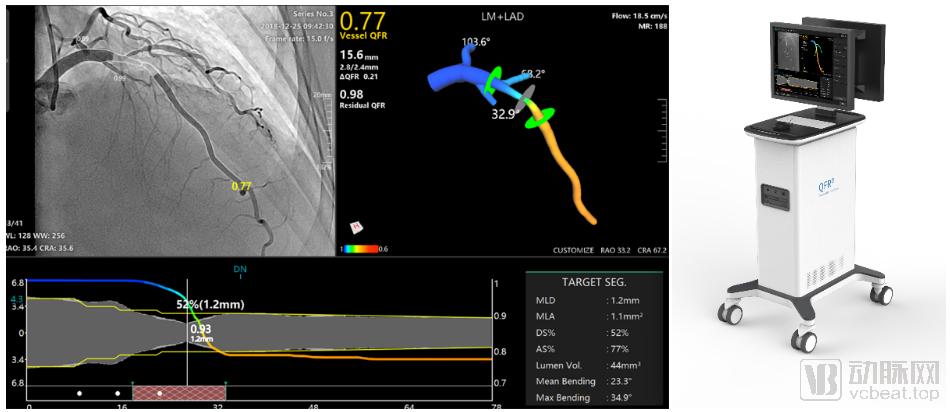

由上海交通大学陈亚珠院士涂圣贤教授团队和博动医学影像科技(上海)有限公司联合自主研发的全球首个QFR冠脉定量血流分数分析技术,可无创、快速、精准地进行冠脉生理学评估,QFR可仅用冠脉造影影像即可快速无创完成功能学计算,从而准确评估心肌缺血程度,同时其独特的PCI手术导航技术将辅助精准治疗策略在国内的快速落地,让各级医院也能具备三甲医院的高年资医生的手术水平。

QFR定量血流分数检测仪是中国原创、国际首创、首个获国家药监局批准上市的国产FFR产品,同时也具备独家的PCI手术导航功能。通过对目前已经发表的超过100项QFR临床研究文献的统计,该技术在全球20多个国家已完成2万多例临床验证数据,也是全球唯一完成大型随机对照临床试验(RCT)的无导丝FFR技术。因此,QFR是目前全球临床证据最足、验证最充分的基于造影的无导丝FFR产品。

而新一代AI-QFR加入了AI的赋能,进一步拓展了其适应症,使得冠脉计算功能学可以更广泛的应用在实际临床工作中。如今,仅需1幅造影、1步计算、1分钟内全自动完成冠脉主支与分支的FFR评估和PCI导航。AI赋能下,新一代技术可以快速、准确完成诊断与PCI手术规划,更适用于实际临床工作流程。2021年发表在循环-心血管介入期刊上的临床研究结果显示,AI-QFR诊断精度已高达93%,将冠心病介入术中诊断精度大幅提升33%。